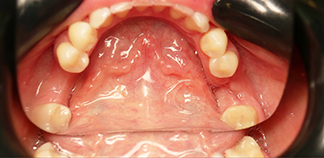

До лечения

Жалобы на разрушенный зуб.

Пациенту 35 лет.

Как лечили

Был удален шестой разрушенный зуб. На его место пересажен восьмой зуб. Через 2 недели проведено эндодонтическое лечение. Изготовлена и установлена коронка на восьмой зуб.

Лечение проведено в течение двух недель.

Лечащие врачи

МАРЧЕНКО (КОСЕВА) Полина Сергеевна, КИСЕЛЕВ Кирилл Эдуардович, МИНОВ Дмитрий Олегович